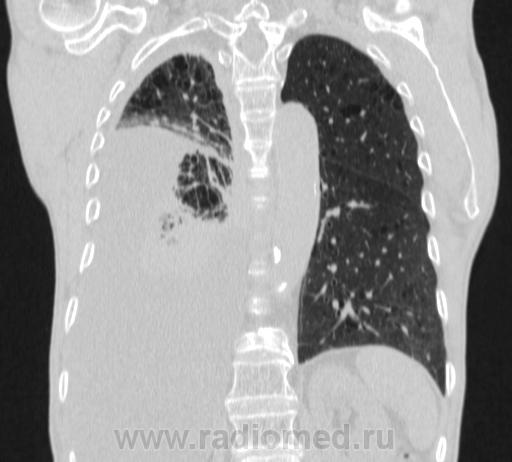

Пожилой мужчина, лечился по н/д правостороннней пневмонии в терап/отделении. Жалобы на одышку, кашель. По результатам Р-контроля после лечения направлен на КТ легких с диагнозом: плеврит справа, распад? В корне правого легкого вижу объёмное образование, с распадом. Смущают размеры плеврита,очень много жидкости, почти до 3 ребра. Анализы крови спокойные- L4,0-6,6, СОЭ 12-16мм. Неужто ТБС, отсев бы был при таком огромном поражении. В посеве мокроты-100% высев клебсиэллы пневмоние. Мокрота на общий анализ в работе-собирает с трудом, изза отсутствия мокроты. Плевральную пункцию еще не проводили. Н азначила бронхоскопию и плеврал пункцию. Как думаете, уважаемые коллеги, это онкопроцесс или тбс распад?

Самое интересное забыла показать- может это 100% навеет на мысль об опухолевом процессе, остеолитическая деструкция позвонка?

Не смотря дайкомы, только по рентгенограмме, предположил бы центральный рак правого легкого. Потому что большой гидроторакс, без смещения средостения в здоровую сторону, как правило, соответствует раковому ателектазу.

По-моему там и слева лимфаденопатия корня легкого, гидроторакс туберкулезной этиологии редко у пожилых бывает

Коллеги, распада там нет, это вас медиастинальное окно подвело. В грудине тоже все в порядке. Да и компрессия позвонка "старая".

Рак.

Небольшое количество увеличенных лимфоузлов, и те - не сказать, чтоб были очень крупными. От эмпиемы до онкологии... Умеренное количество жидкости в перикарде, толщиной слоя до 13-14 мм. При подобной картине не вижу смысла гадать по сжатому лёгкому, пишу так: массивный выпот справа, около 2500 мл, диафрагма оттеснена жидкостью каудально, печень (!!!) смещена каудально и вправо. Легкое справа значительно компрессировано жидкостью, оценка проходимости бронхов и состояния легочной паренхимы (кроме имеющейся эмфиземы) практически невозможна. Необходима пункция плевральной полости справа (цитология, ВК, посев на микрофлору и проч), КТ-контроль после эвакуации жидкости.